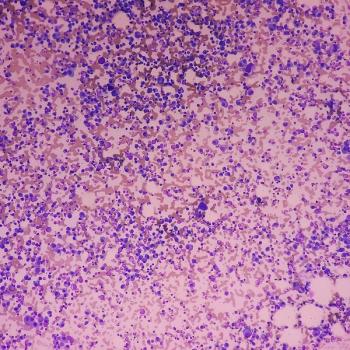

Patients with intermediate- or high-risk MDS experienced a higher modified overall response rate with the venetoclax/azacitidine vs placebo/azacitidine.